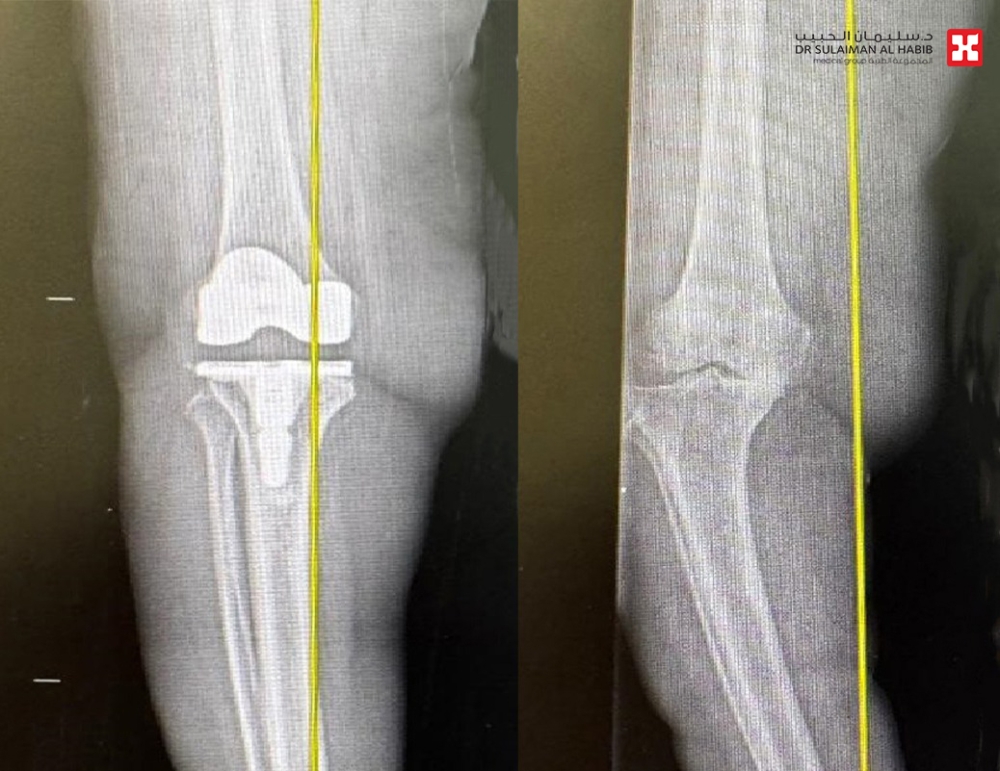

وأضاف أن المراجعة خضعت لفحوصات دقيقة، حيث كشفت صور الأشعة السينية عن وجود خشونة حادة في مفصل الركبة، وتلف بالأربطة، فقام الفريق الطبي بوضع خطة علاجية متكاملة، بعلاج هشاشة العظام، بعدها أخضعت لعملية متقدمة باستخدام تقنية الروبوت الجراحي، وتحت التخدير النصفي، وتم فيها تعديل التقوس الحاد باستخدام دعامة لتعويض تصلب وضعف الأربطة، ومن ثم استبدال مفصل الركبة بآخر صناعي عالي الجودة ومناسب للحالة. استغرقت العملية نحو “90” دقيقة، وتكللت ولله الحمد بالنجاح التام، وتمكنت المراجعة من المشي بعد ساعات قليلة من العملية، وغادرت المستشفى بعد عدة أيام، وهي بحالة صحية جيدة، ولاحقاً تخلصت من كافة الأعراض التي عانت منها طوال عامين، وعادت لممارسة حياتها الطبيعية.